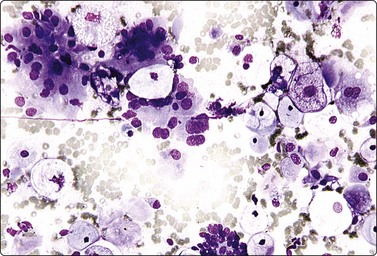

Embryonal carcinoma (Figs 13.33 and 13.34)14,58-61,63,65,66

image image

Fig. 13.33 Embryonal carcinoma

(A) Adenocarcinoma-like tissue fragment of large malignant cells with large vesicular nuclei, coarse chromatin, prominent nucleoli; prominent cytoplasmic vacuolation (MGG, HP); (B) Fragment of undifferentiated mesenchymal tissue right; cluster of malignant epithelial cells with large vesicular nuclei and prominent large nucleoli (H&E, HP) left.

Criteria for diagnosis

Cell-rich smears,

Frequent three-dimensional clusters,

Occasional tendency to acinar and microglandular grouping,

Large vesicular, obviously malignant nuclei, large nucleoli,

Indistinct cell borders,

Basophilic to amphophilic, sometimes pale, vacuolated cytoplasm,

Immunocytochemistry: cells positive for PLAP, OCT 3/4, CD30, AE1/AE3 and CK7.

The vesicular nuclei of embryonal carcinoma are larger and more pleomorphic than those of seminoma, the chromatin is coarse and irregular and nucleoli are large, occasionally huge, and eosinophilic. The cytoplasm is pale and distinctly vacuolated, but not ‘bubbly’. It is not highly fragile and a TB as in seminoma is not seen. Cytoplasmic boundaries are poorly defined (Fig. 13.33). Hemorrhage and tumor necrosis may be prominent and may hamper the identification of diagnostic cells. It is usually not seen in smears of seminoma. Chromatin threads and reticulated material resembling TB can occur. Large syncytiotrophoblastic cells may be found. Prominent lymphoid/plasma cell infiltrates or mucus are not seen. The presence of cellular mesenchyme on its own does not warrant a designation of teratoma (Figs. 13.33B and 13.34).49